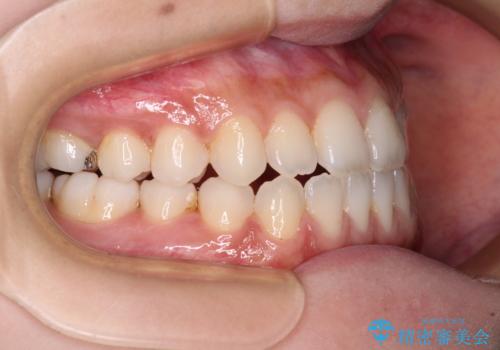

舌突出癖で口元が開いてしまう 舌トレーニングを行ったインビザライン矯正

- 前歯の上下スペースと前歯の隙間を気にして来院された患者様です。

インビザラインにより上下の前歯の隙間を閉じていくこととしました。

上下の隙間に舌が入り込むことが、すきっ歯やオープンバイトの原因であったため、舌の筋肉のトレーニングも並行して行い、後戻りの抑制を図りました。